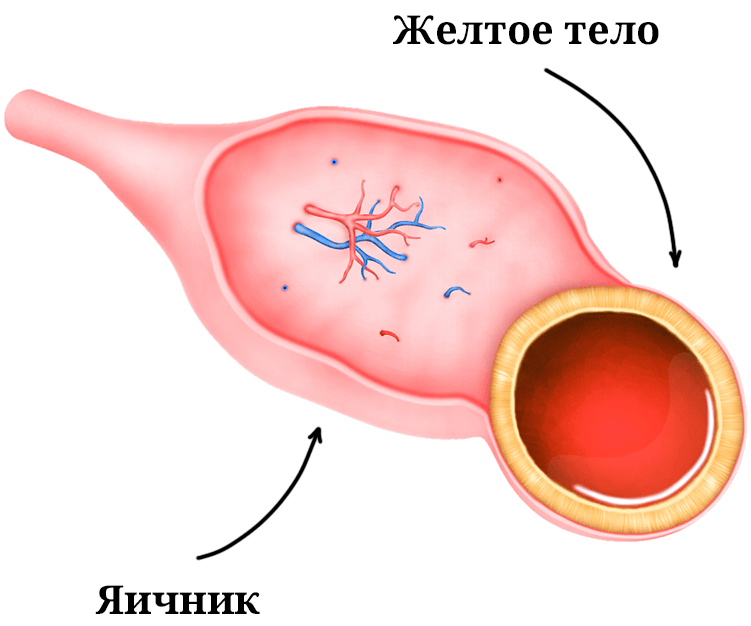

Гистологические изображения фолликулярной кисты яичника